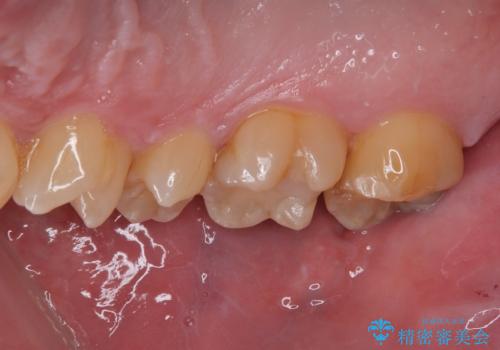

- 金属の詰め物が外れたので、虫歯の治療がしたいとのことで来院された患者様です。ほかの部位の治療などもあったため、コンポジットレジンによる応急処置を初診時に行いました。

ほかの部位の治療が一段落ついたのでセラミックインレー修復による虫歯治療を行っていくことにしました。

見た目、機能面共に大変喜んでいただきました。